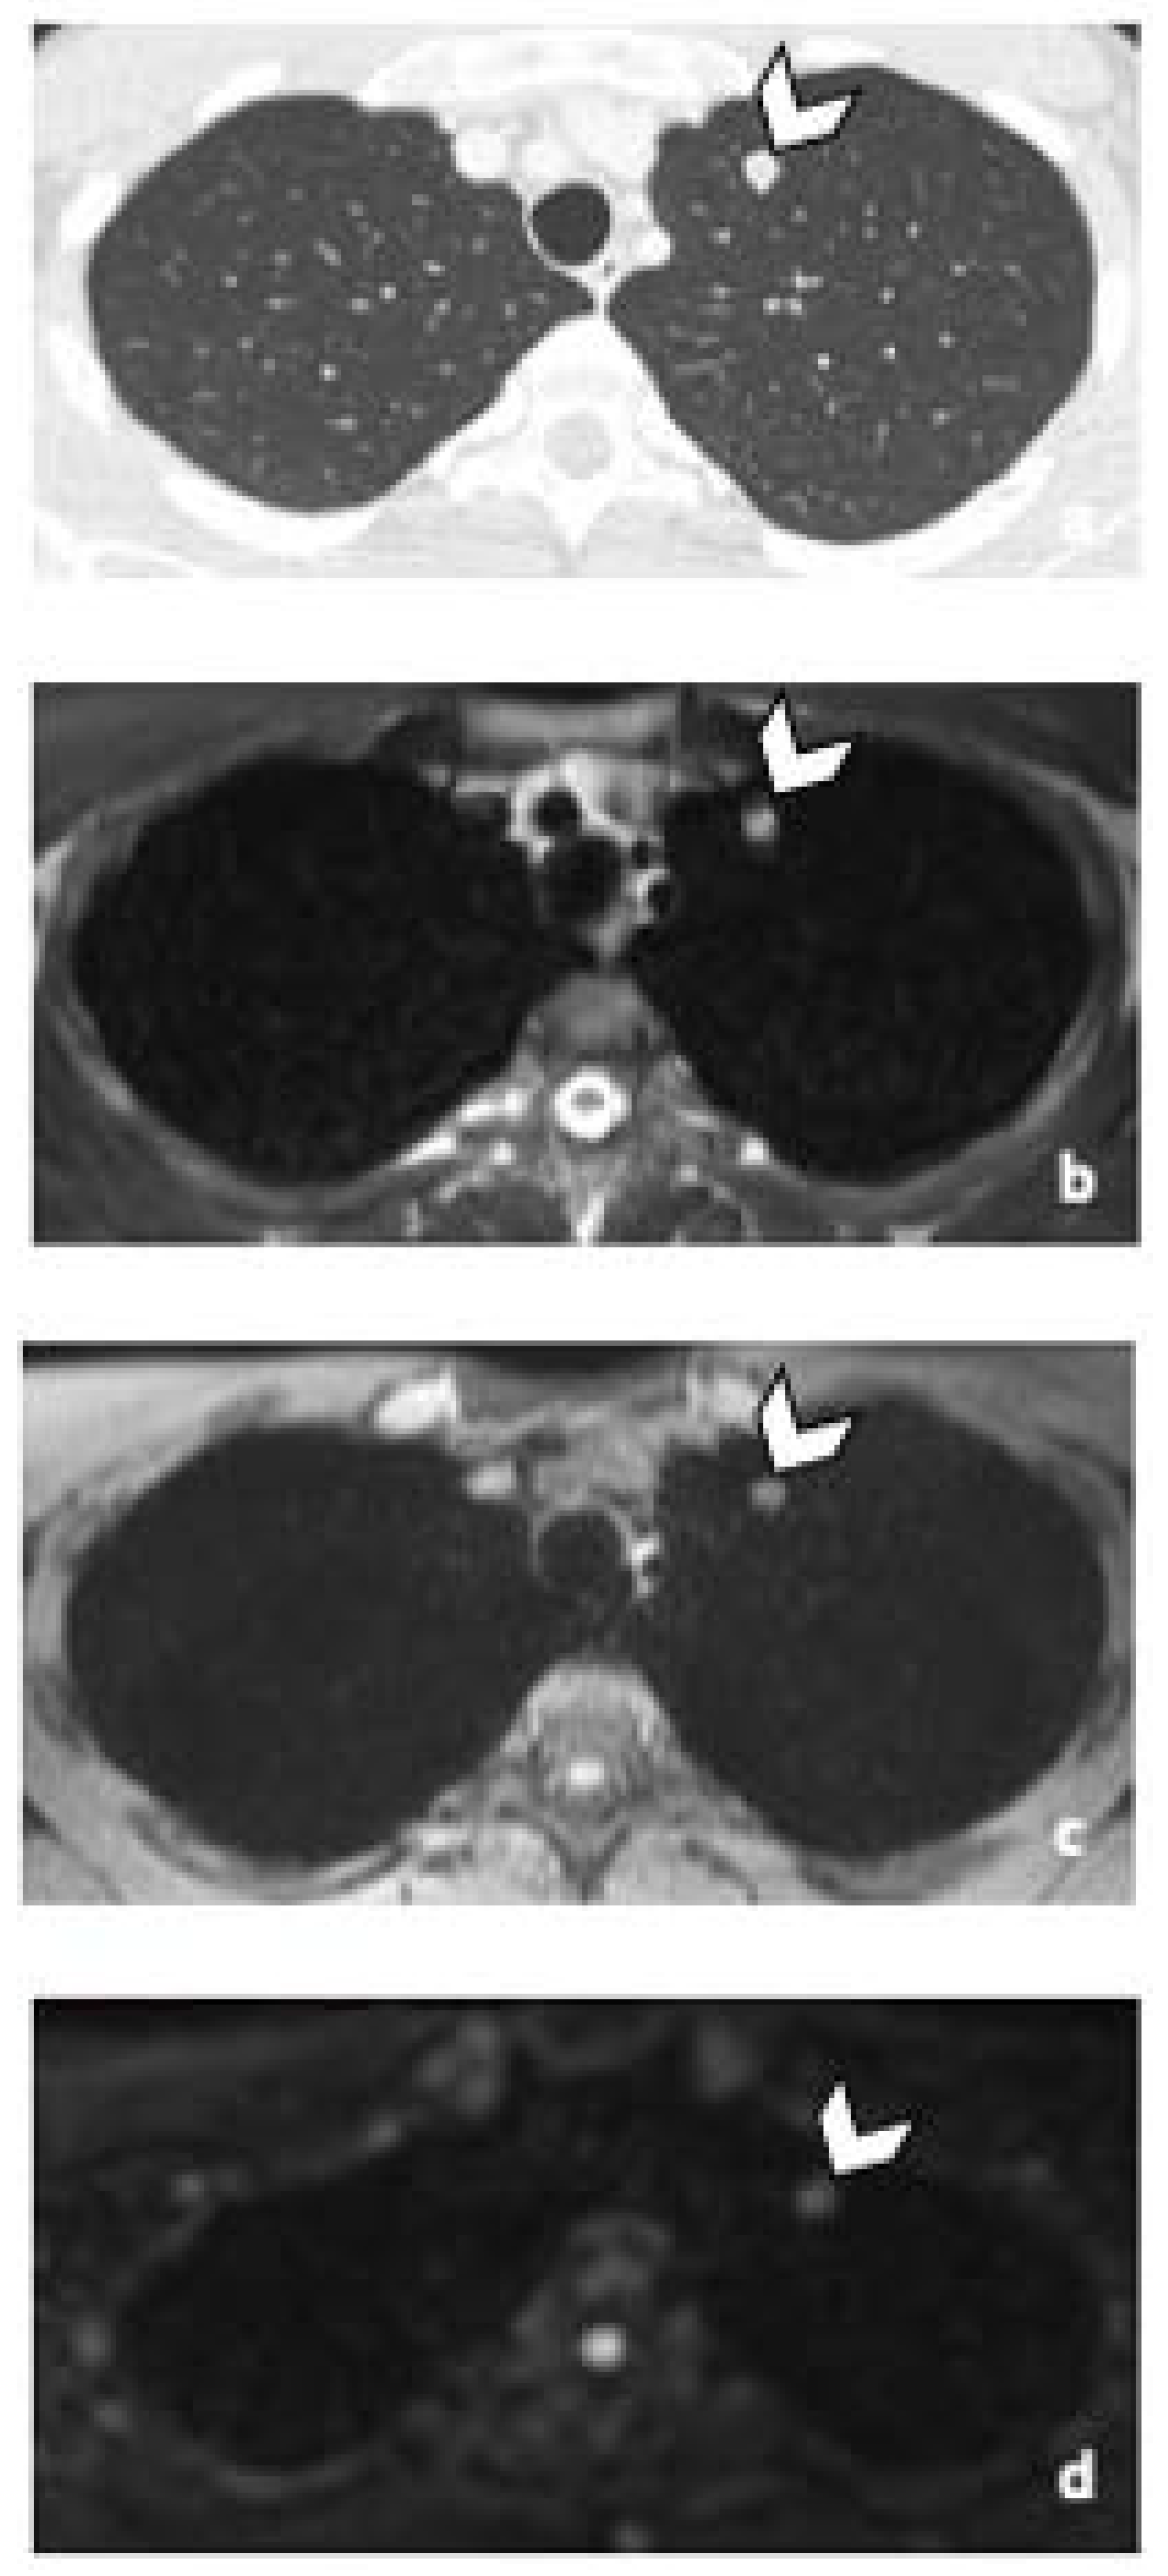

3.3.2. DLN Metastases